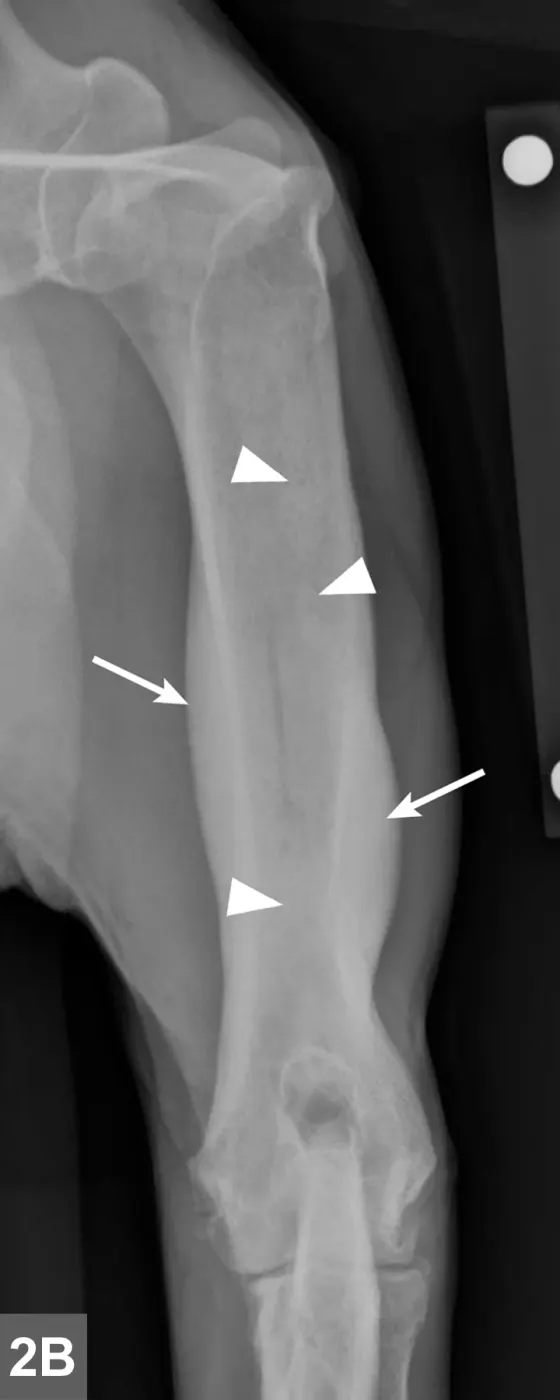

Radiographic signs of panosteitis frequently lag days to weeks behind clinical signs.1,3 The earliest radiographic sign of panosteitis is a decrease in opacity around the nutrient foramen. Later signs include an increase in mineral opacity within the medullary canal of long bones and loss of the normal trabecular bone pattern (Figure 1). Smooth periosteal and endosteal new bone may also be seen in more severe cases (Figure 2). Radiographs of the affected limb may be compared with those of the contralateral limb to assist in diagnosis. Nuclear scintigraphy may assist in diagnosis in cases in which radiographic changes have not yet developed.4

Lateral radiographic projections of the femur (A) and ulna (B, next slide) in dogs with early signs of panosteitis. Note the radiolucency around the nutrient foramen (arrows) and increased opacity within the medullary canal (arrowheads) in both cases.